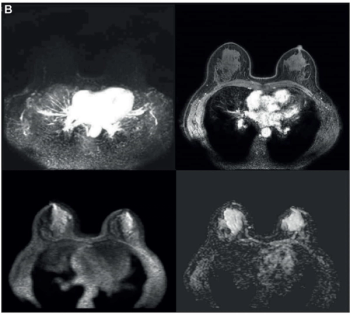

In a recent interview, Sherry Shen, M.D., discussed the potential impact of FES PET recently being recommended by the National Comprehensive Cancer Network (NCCN) Guidelines for the staging of recurrent or metastatic estrogen receptor-positive (ER+) lobular breast cancer.